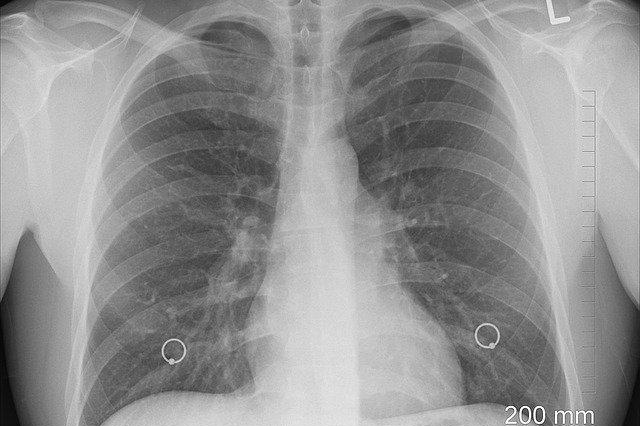

※ 폐암 초기증상 10가지

폐는 호흡을 통하여 체내에 산소를 유입하고 이산화탄소를 배출하는 역할을 합니다. 이렇게 중요한 역할을 하는 폐에 악성 종양이 생기면 폐암의 발병률이 높아지는데, 폐암이 진행된 이후에도 기침이나 가래 정도로 가벼운 감기 증상만 나타날 수 있어서 진단도 쉽지 않고 쉽게 알아챌 수 없으며, 폐암 발병의 주요 원인은 흡연 때문인데, 이런 이유로 주로 남성에게 많이 발생한다고 합니다. 폐암은 대부분 선천적인 요인은 드물고, 주로 후천적인 요인으로 발병한다고 합니다. 최근에는 외부로부터의 미세먼지와 중금속, 석면 등의 유해한 물질에 노출되는 등 주변의 환경적인 요인이 발병의 원인이 된다고도 합니다. 간접흡연도 여러 복합적인 환경 요인과 더불어서 여성에게도 점차 발병률이 높아진다고 합니다. 특히, 폐암은 우리나라 암 사망률 1위로 생존율이 낮은 암 중 하나로 꼽히는데, 조기 발견과 치료가 매우 중요하다고 합니다. 그래서 일상 속에서 폐암 초기 증상을 간과하지 않도록 주의해야 하는데, 폐암의 초기 증상은 어떤 것이 있는지 알아봅니다.

폐암 초기 증상